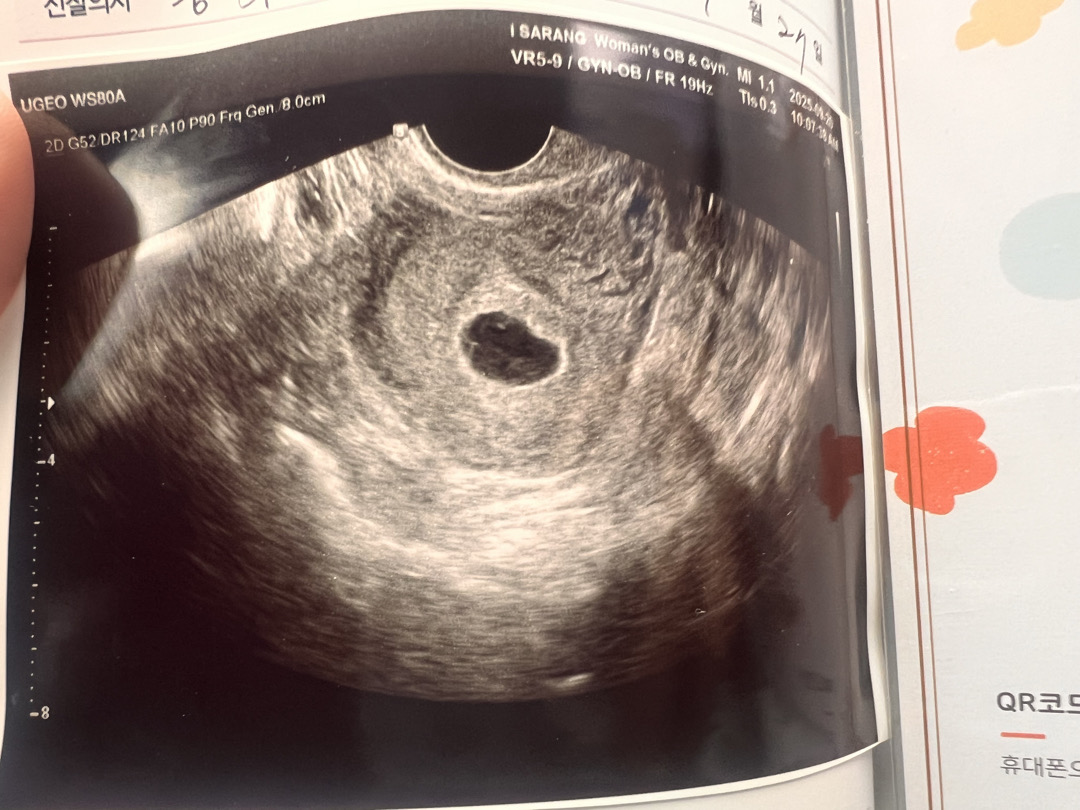

아기집1개, 난황2개 쌍둥이 일까요?

오늘 5주차 6일이고 초음파봤더니 아기집안에 난황이 두개 보였어요 다음주 되어야 더 정확하겠지만 쌍둥이일 확률도 있다고 하셨는데 위험하지 않을까 걱정되네용 ㅠ 원래 걱정인형이 아니었는데 참😂 어떻게 보이시나요??